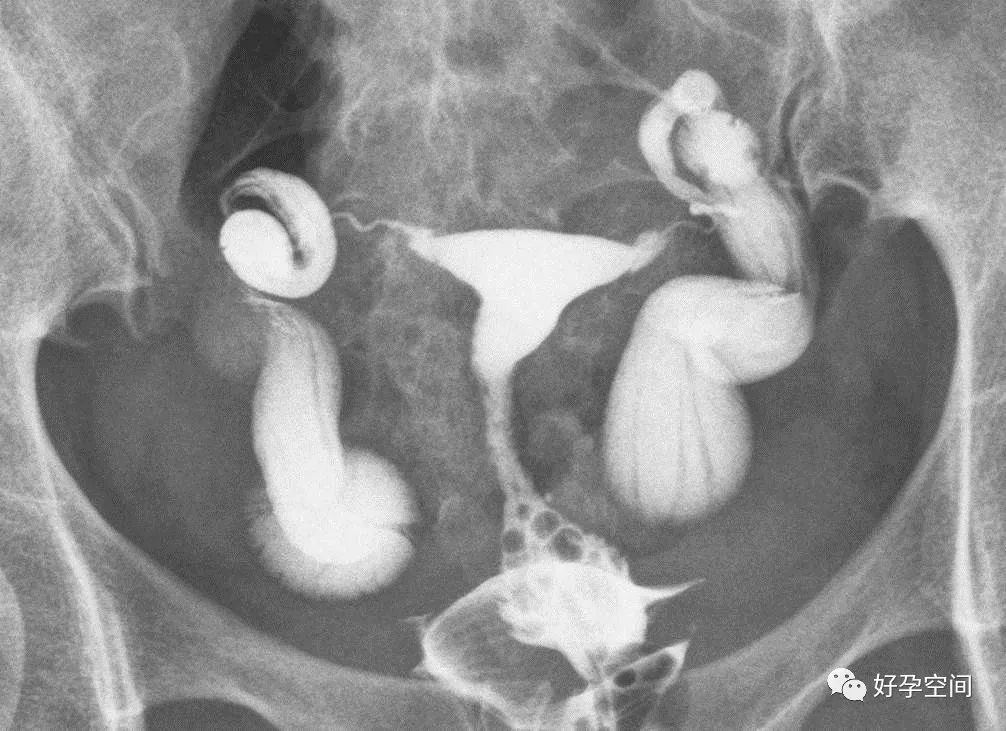

5、正常输卵管走行:正常的输卵管是从子宫角的尖端起,呈自然流线形,输卵管走行不固定,两侧输卵管不一定对称,输卵管活动度很大,走行分四型:(1)上行,和宫体连接呈缠绕状,在子宫底两侧弯弯曲曲上行,壶腹部远段和伞部向下屈曲。(2)反向走行,一侧上行,另一侧下行。(3)下行,和宫体连接呈缠绕状,在子宫两侧弯弯曲曲下行,壶腹部远段和伞部向上屈曲。(4)水平走行,在宫底水平向两侧呈伸展状。

双侧输卵管下行

双侧输卵管水平走行